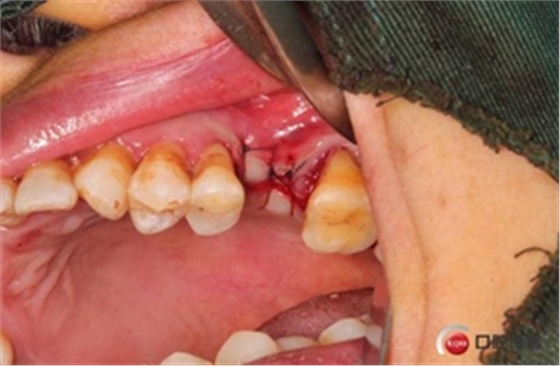

大家好,我是梁老師的助理小依。由于梁老師每天手術(shù)檔期安排較滿,加上經(jīng)常出差講課,沒有時間整理病例 。為了方便大家更及時的了解梁老師最新手術(shù)動態(tài),以后將由我為大家整理并推送梁老師最新經(jīng)典案例。案例文字旁白少,但圖片會盡量完整展示手術(shù)全過程,供大家學(xué)習(xí)參考。有任何問題,可以留言,梁老師會親自為大家解答。感謝大家對梁老師的支持和關(guān)注!